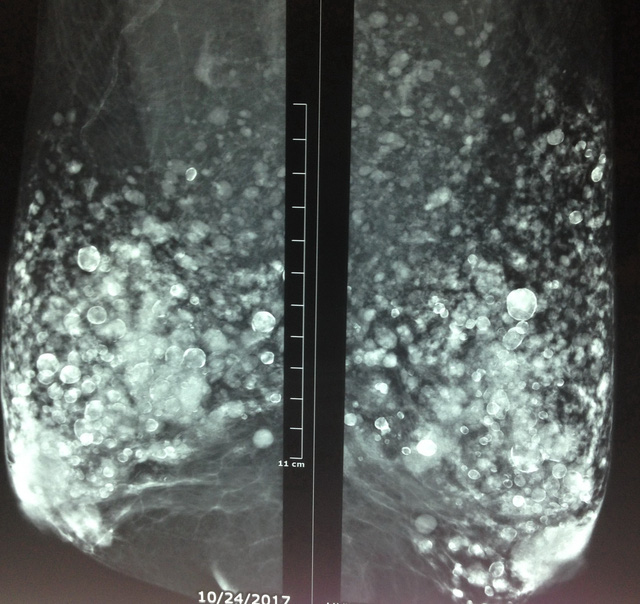

Hình chụp nhũ ảnh cho thấy hai bầu vú của bệnh nhân "nở ngàn bong bóng" - Ảnh: Bác sĩ Phan Thanh Hải cung cấp

Khi bác sĩ chụp xquang hỏi lâm sàng thì bà T. khai thật là năm xưa, cách đây khoảng 40 năm có nghe lời một y tá vườn "chích dầu" vào hai bên vú để làm to lên và bà không biết đó là silicon đã tồn tại trong vú suốt mấy chục năm qua.

Hiện bệnh nhân được bác sĩ đề nghị làm thêm chẩn đoán hình ảnh khác như chụp cộng hưởng từ hai vú để kiểm tra kỹ hơn và truy tìm xem bà T. có bị ung thư vú hay không./.